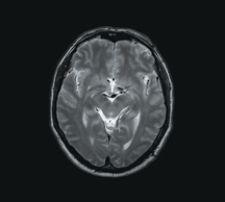

T2W TSE with 0.6 mm in-plane resolution acquired with 3.0 mm slices courtesy of Philips Medical Systems

High-Field MR Accelerates Neurological Imaging

Neurology is one field that is really beginning to apply the advantages of 3.0 T MR toward its diagnostic purpose. Increased SNR of high-field MRI allows more detailed visualization of smaller vessels in the brain. Using identical acquisition parameters, 3.0 T can show small vessels that are not even visible with a 1.5 T.

“[Increased field strength] is very good when you are trying to look at angiography of the brain, which is important for tumor growth because when you have tumors growing, they form their own feeding vessels,” said John Patrick, general manager, Philips MRI. “You can visualize that much better at a higher field strength.”

MR of any field strength can image both surface and deep brain structures with a high degree of anatomical detail, and can detect small changes in these structures. Also, a radiologist can discover how a normal, diseased or injured brain is working with functional MRI (fMRI). fMRI sees images of blood flow in the brain as it is occurring, allowing the visualization of changes in brain activity as patients perform various tasks, such as thought, speech, movement and sensation. The radiologist can then determine what part of the brain is used for each specific function, which can be a valuable tool for treatment planning.